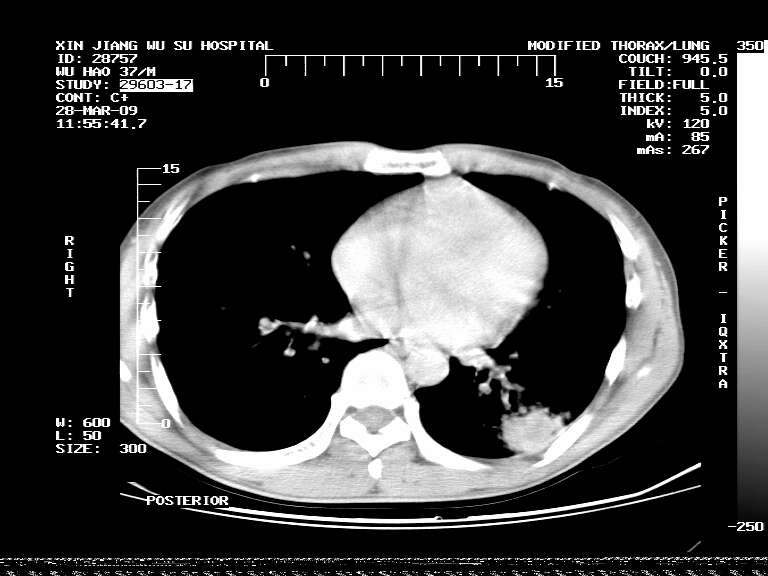

男,37岁,体检胸透发现阴影。

患者体检发现 无症状 左肺下叶占位,边缘模糊,可见血管聚束、分叶、胸膜牵拉,增强呈不均匀性强化。 首先考虑左肺下叶周围型肺癌,建议穿刺活检。

左肺下叶见一结节病变,边缘欠清不光滑,与胸膜粘连且胸膜局限性增厚,注药后呈环形强化,动脉期壁呈明显点环状强化,静脉期壁强化减低,中心密度低无强化,灶周无明显的卫星灶和水肿区(晕征)---考虑周围性肺癌,不除外感染性病变,建议穿刺活检。

左肺下叶软组织病灶,密度较高,内见点状钙化,其周围见子灶,邻近胸膜扁平样增厚.c+病灶强化明显,中心强化弱.诊断:左肺下叶结核瘤.

左肺下叶大片实变影,内靠胸膜见不规则更高密度结节灶,边缘强化,相邻胸膜增厚,胸膜下脂肪线存在。考虑炎症,结核可能。